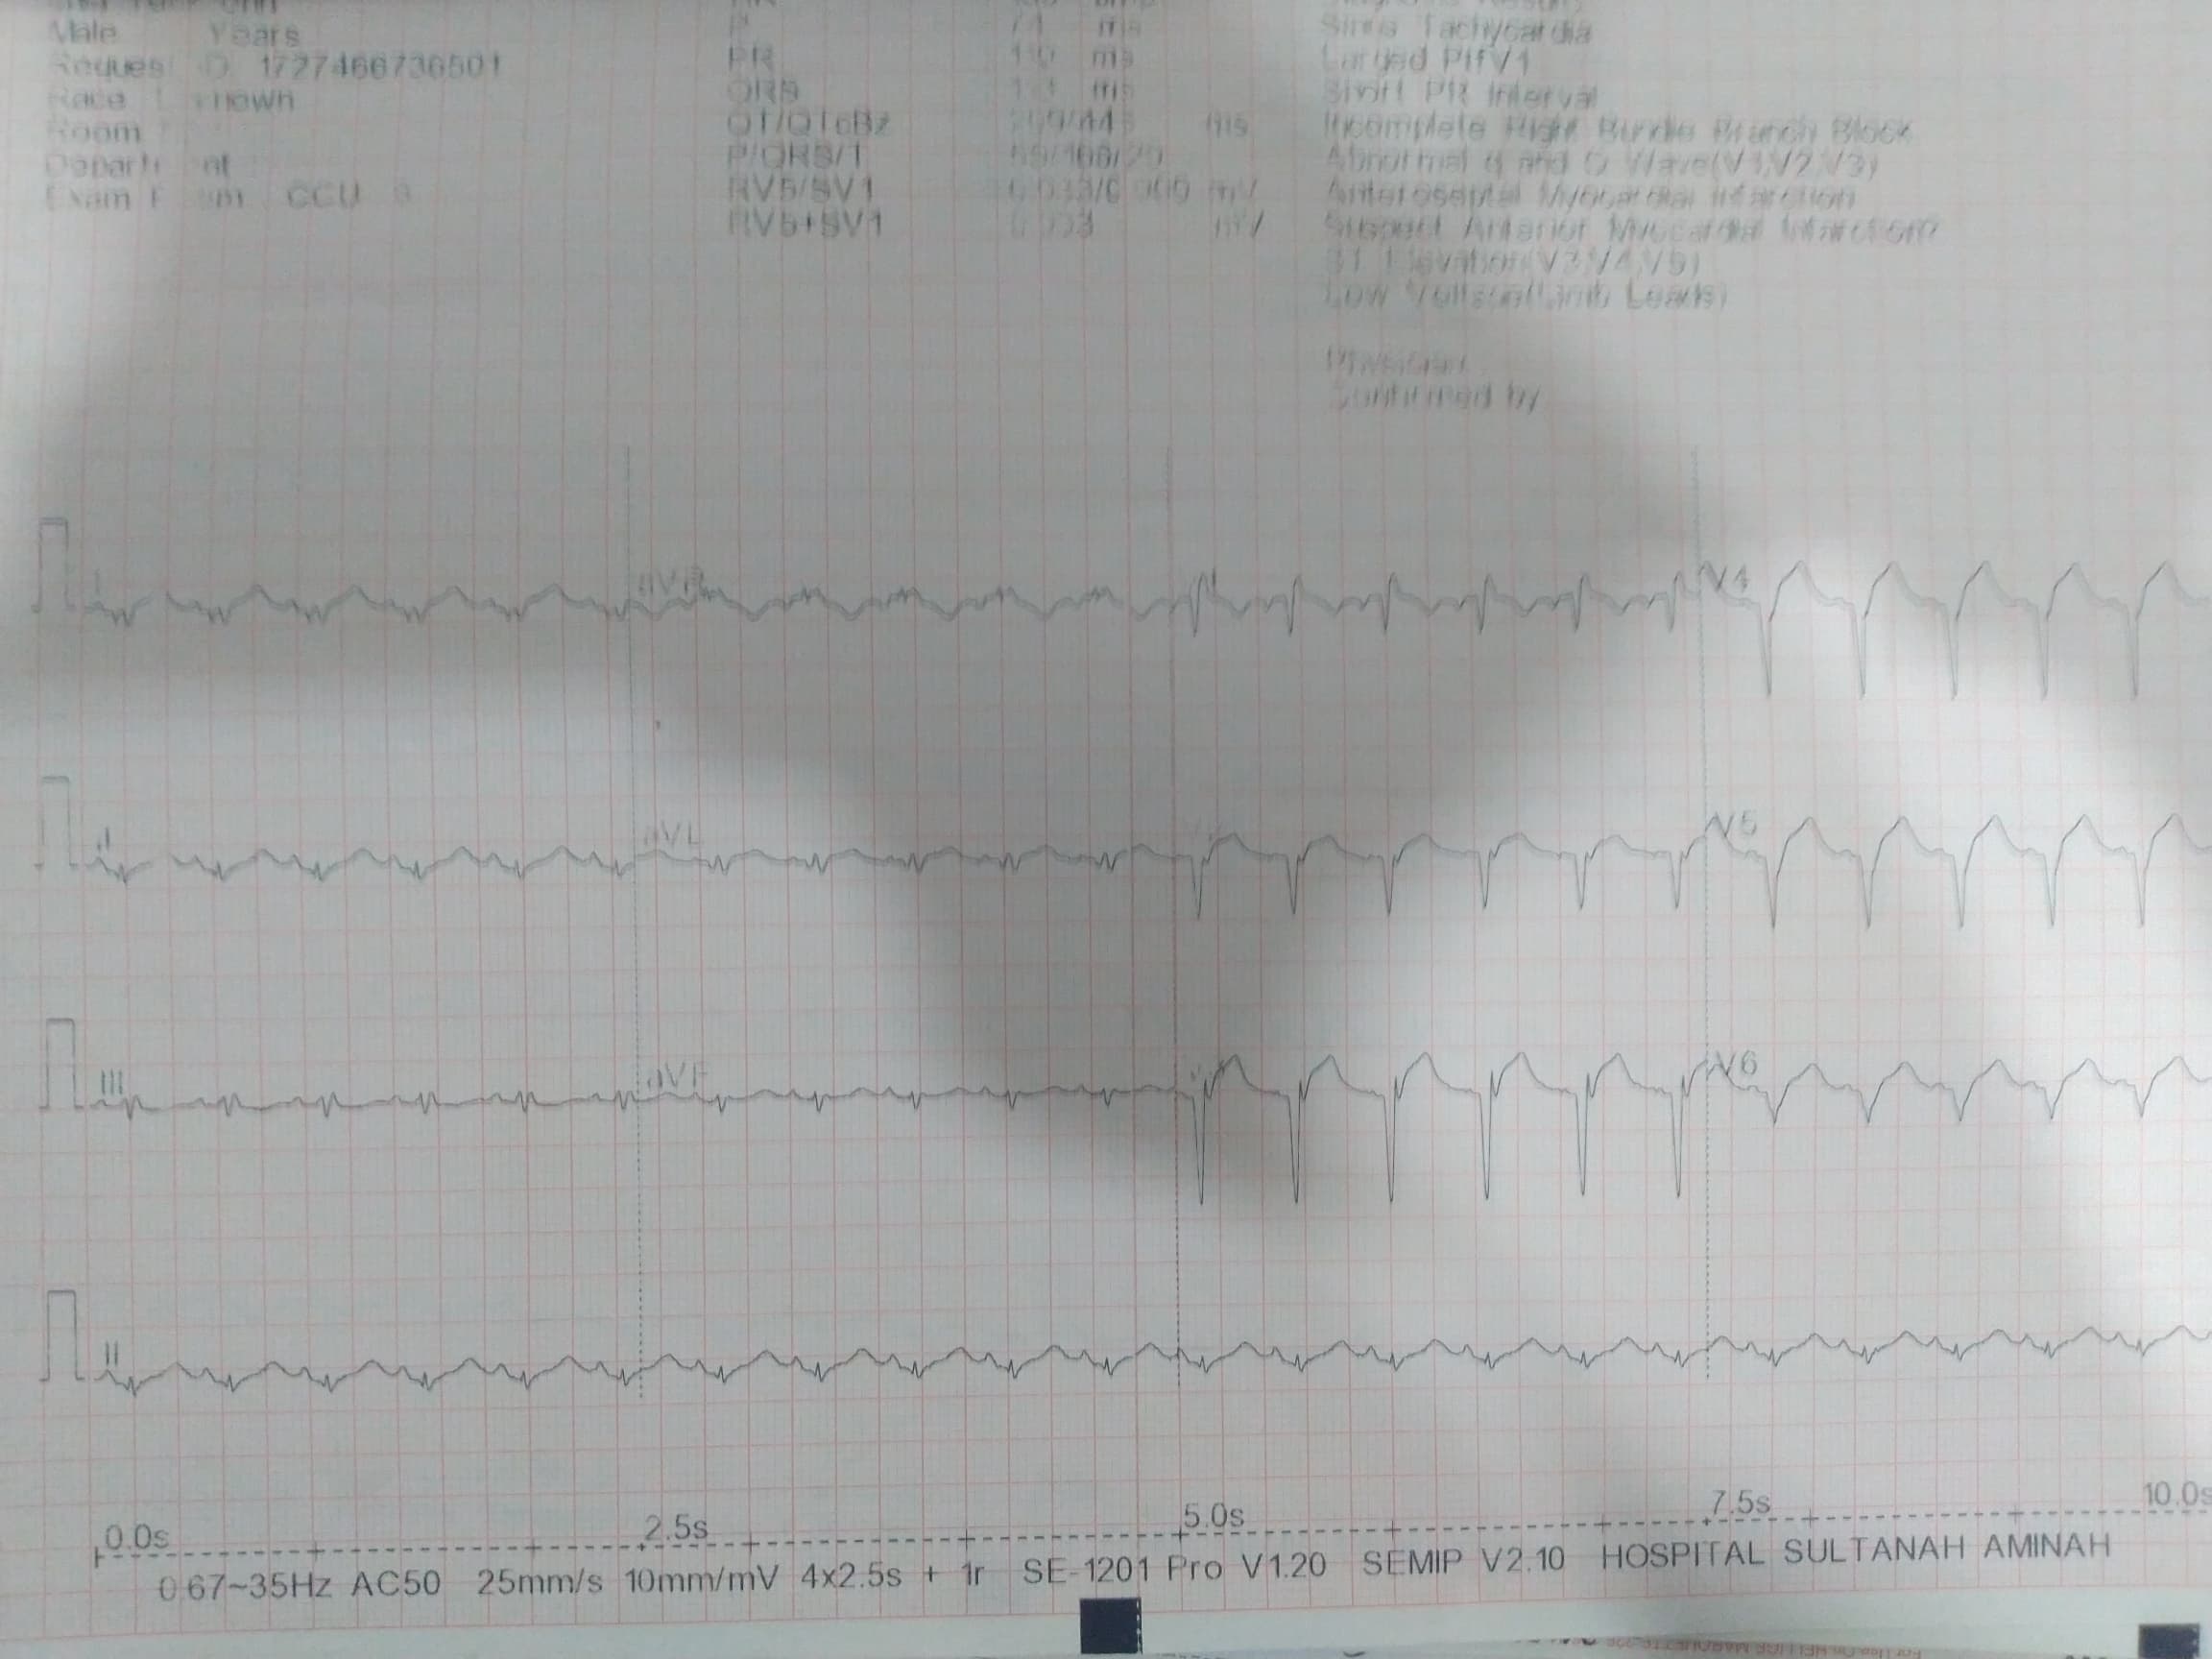

Relevant Test Results Prior to Catheterization

His electrocardiogram on admission showed sinus rhythm with deep Q wave over lead V1 to V6 with ST elevation of 3mm. His Trop T was 78454 ng/L and creatinine kinase was 692 U/L. His lactate dehydrogenase was 1256 U/L. He had mild acute kidney injury with creatinine level of 114 micromoles/L. His total cholesterol was 4.5mmol/L and low density lipoprotein was 2.8 mmol/L. The fasting blood glucose level was 3 mmol/L. Otherwise, the liver function test and electrolytes levels were unremarkable.